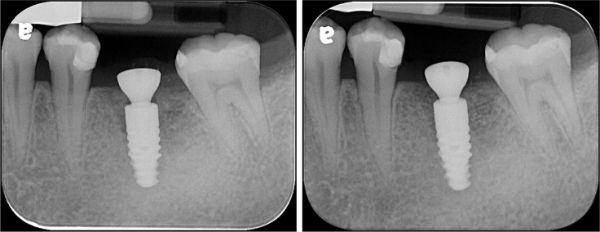

術後X光

術前、術後比較